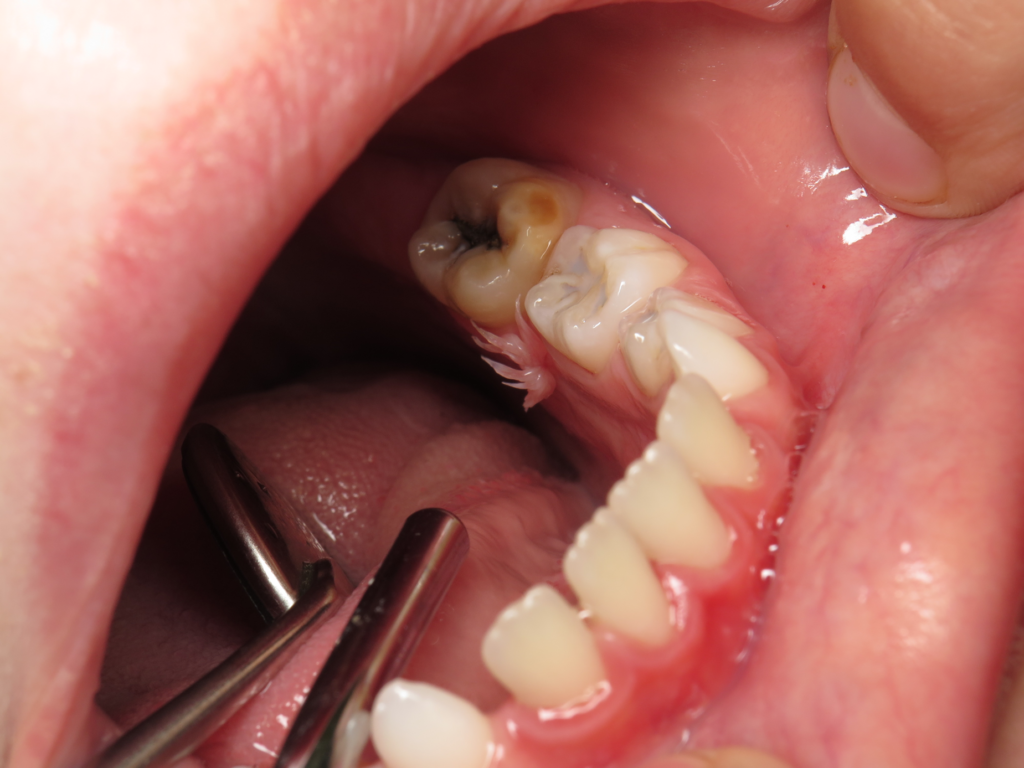

8-year-old boy with discolored teeth

An 8-year-old patient presented at the pediatric dentist’s office because of the “unusual” color of his teeth.